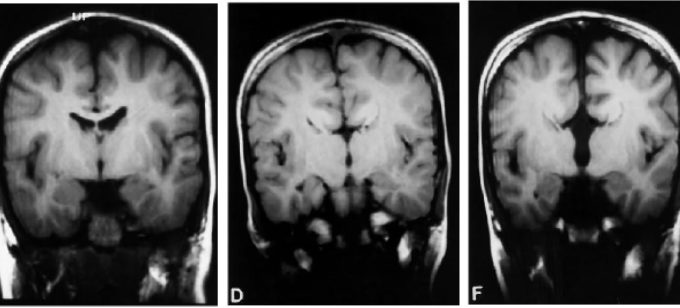

[Patente de Invención] “Un método para procesar imágenes cerebrales”: el desafío de detectar la Epilepsia tempranamente

Noticias